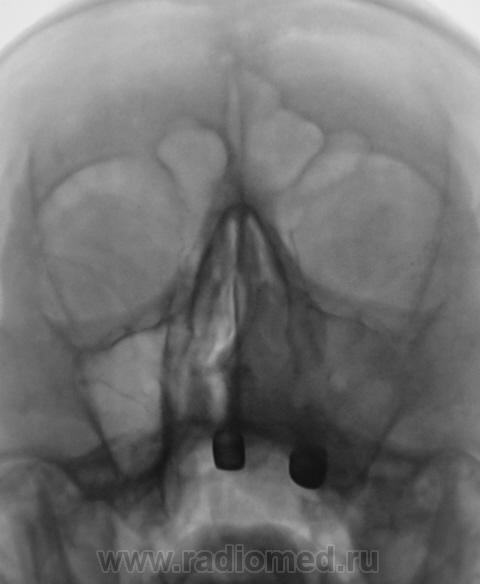

Четвертый срез.

Последний срез.

Увеличение обьема - однозначно....

На мой взгляд, информативные срезы 4 и 5, ну, конечно, обработанный 3!

какое нибудь мукоцеле)))))))))

А, не много-ли для мукоцеллле?

а что, при мукоцеле пазуха тоже в объеме может увеличиваться и стенки пазухи страдают (космтные эрозиии и все такое)........

Пациент, сейчас, в областном онкологическом диспансере